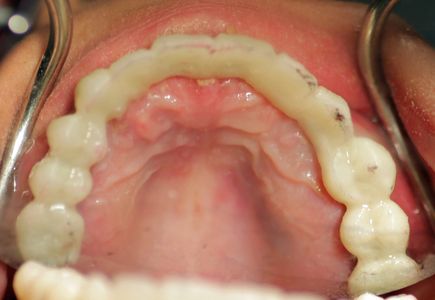

Cristina returns early on Day Two. Her upper temporary teeth have milled overnight and are ready to be cemented in.

Dr. Gibney checks how the bite between the upper and lower temporary teeth fit. You can see the marks on Cristina's teeth from checking the bite.

Some gentle drilling is done to make the upper and lower teeth have a compatible bite.